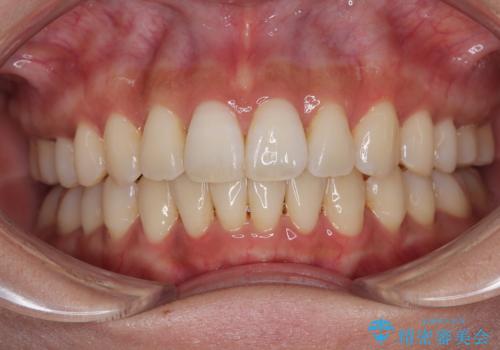

![[突き出た前歯を引っ込めたい] ワイヤー矯正とマウスピース矯正の併用治療の症例 治療後](https://seimitsushinbi.jp/wp/wp-content/uploads/2024/08/IMG_9725-500x350.jpg?v=1723179307)